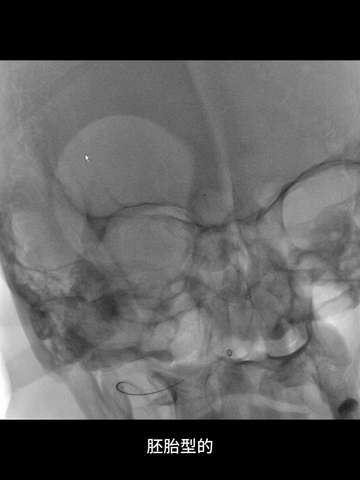

5、经桡鞘,选择中间管建立治疗通路,内衬4F长多功能管,利用其头端指向性辅助微导丝超选,及其支撑性助力上高微导管和中间管。

7、术前CTA示双侧胚胎型后交通,故微导丝和微导管未尝试超选大脑后动脉,微导管头端置于基底动脉远端。

8、考虑到双胚胎后交通时,基底动脉管径一般比较小,故回收取栓支架时6F中间管只是行至基底动脉近端,未敢深入其中。

CTA:基底动脉闭塞,双侧胚胎型后交通,基底动脉尖部可见造影剂充盈;弓上血管迂曲明显,双侧椎动脉V1段均见明显曲折,左侧椎动脉颅内段显影不清,但可见右侧椎动脉颅内段延续至基底动脉闭塞近端。